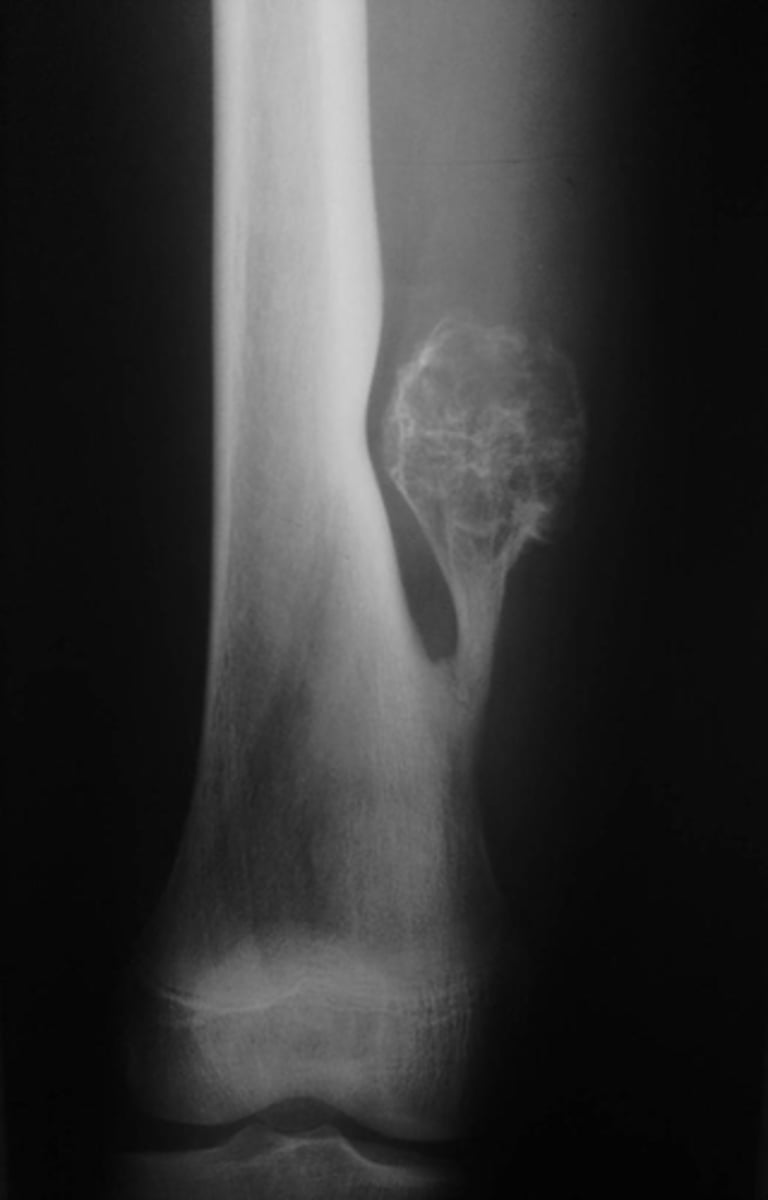

Lateral proximal tibia

Bone

<p>Bone</p>

- Longitudinal: epiphysis/metaphysis (up to joint surface)

- Eccentricity: eccentric

- Transverse: medullary

Location

<p>Location</p>

- Lytic

- Geographic

- Short zone of transition

Behavior

<p>Behavior</p>

Cortex

<p>Cortex</p>

7

New cards

Nothing visible

Matrix

<p>Matrix</p>

Giant cell tumor

Most likely diagnosis?

<p>Most likely diagnosis?</p>

Refer to orthopedist or oncologist

Next step?

<p>Next step?</p>

Could be aggressive (20%)

Concerns/complications?

<p>Concerns/complications?</p>